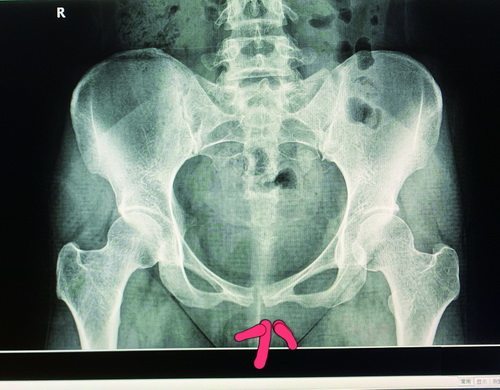

改良经皮逆行耻骨上支或髋臼前柱髓内螺钉置入技术及其应用示例

图片尺寸1080x811